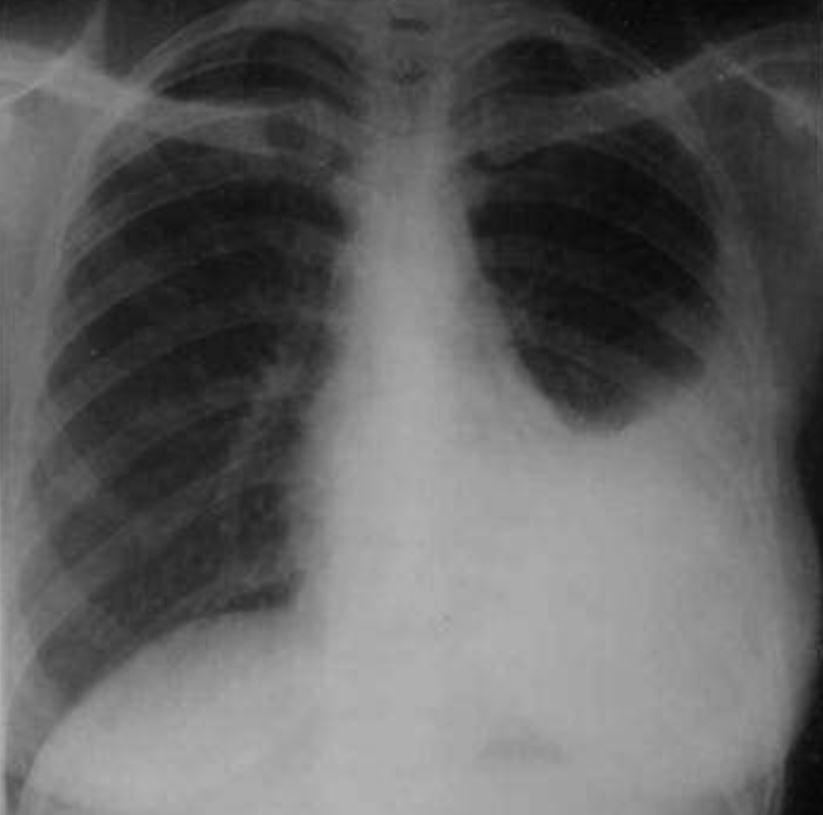

Juru x-ray berserta mesin x-ray mudah alih (portable x-ray) dipanggil.

Hasil keputusan x-ray menunjukkan paru-paru kiri Ali dipenuhi cecair.

Doktor segera membuat keputusan untuk “menebuk” paru-paru Ali.

Prosedur tersebut adalah thoracocentesis, iaitu cecair di ruangan pleura yang menyelimuti paru-paru Ali, perlu dikeluarkan.

Cecair ini sedang menekan paru-paru Ali menyebabkan ia tidak dapat kembang sepenuhnya.